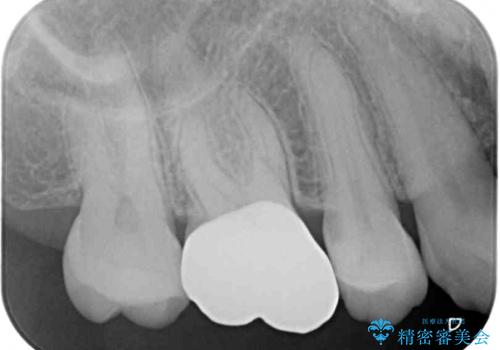

診査の結果、不適合な銀歯の隙間からむし歯が進行しており、更には頬側、口蓋側ともに歯肉縁付近に強い知覚過敏症状が認められました。

健全歯質が多いため、インレーおよびむし歯を除去した上で知覚過敏を緩和させる処置を行うことが望ましいと判断されましたが、知覚過敏の症状が一向に改善されないため、全体をセラミッククラウンで補綴することとしました。

セラミッククラウンを装着する前に仮歯を装着しましたが、その時点で強い痛みはほぼ改善され、セラミッククラウン装着後には痛みはもちろん、しみる症状も感じることがなくなりました。